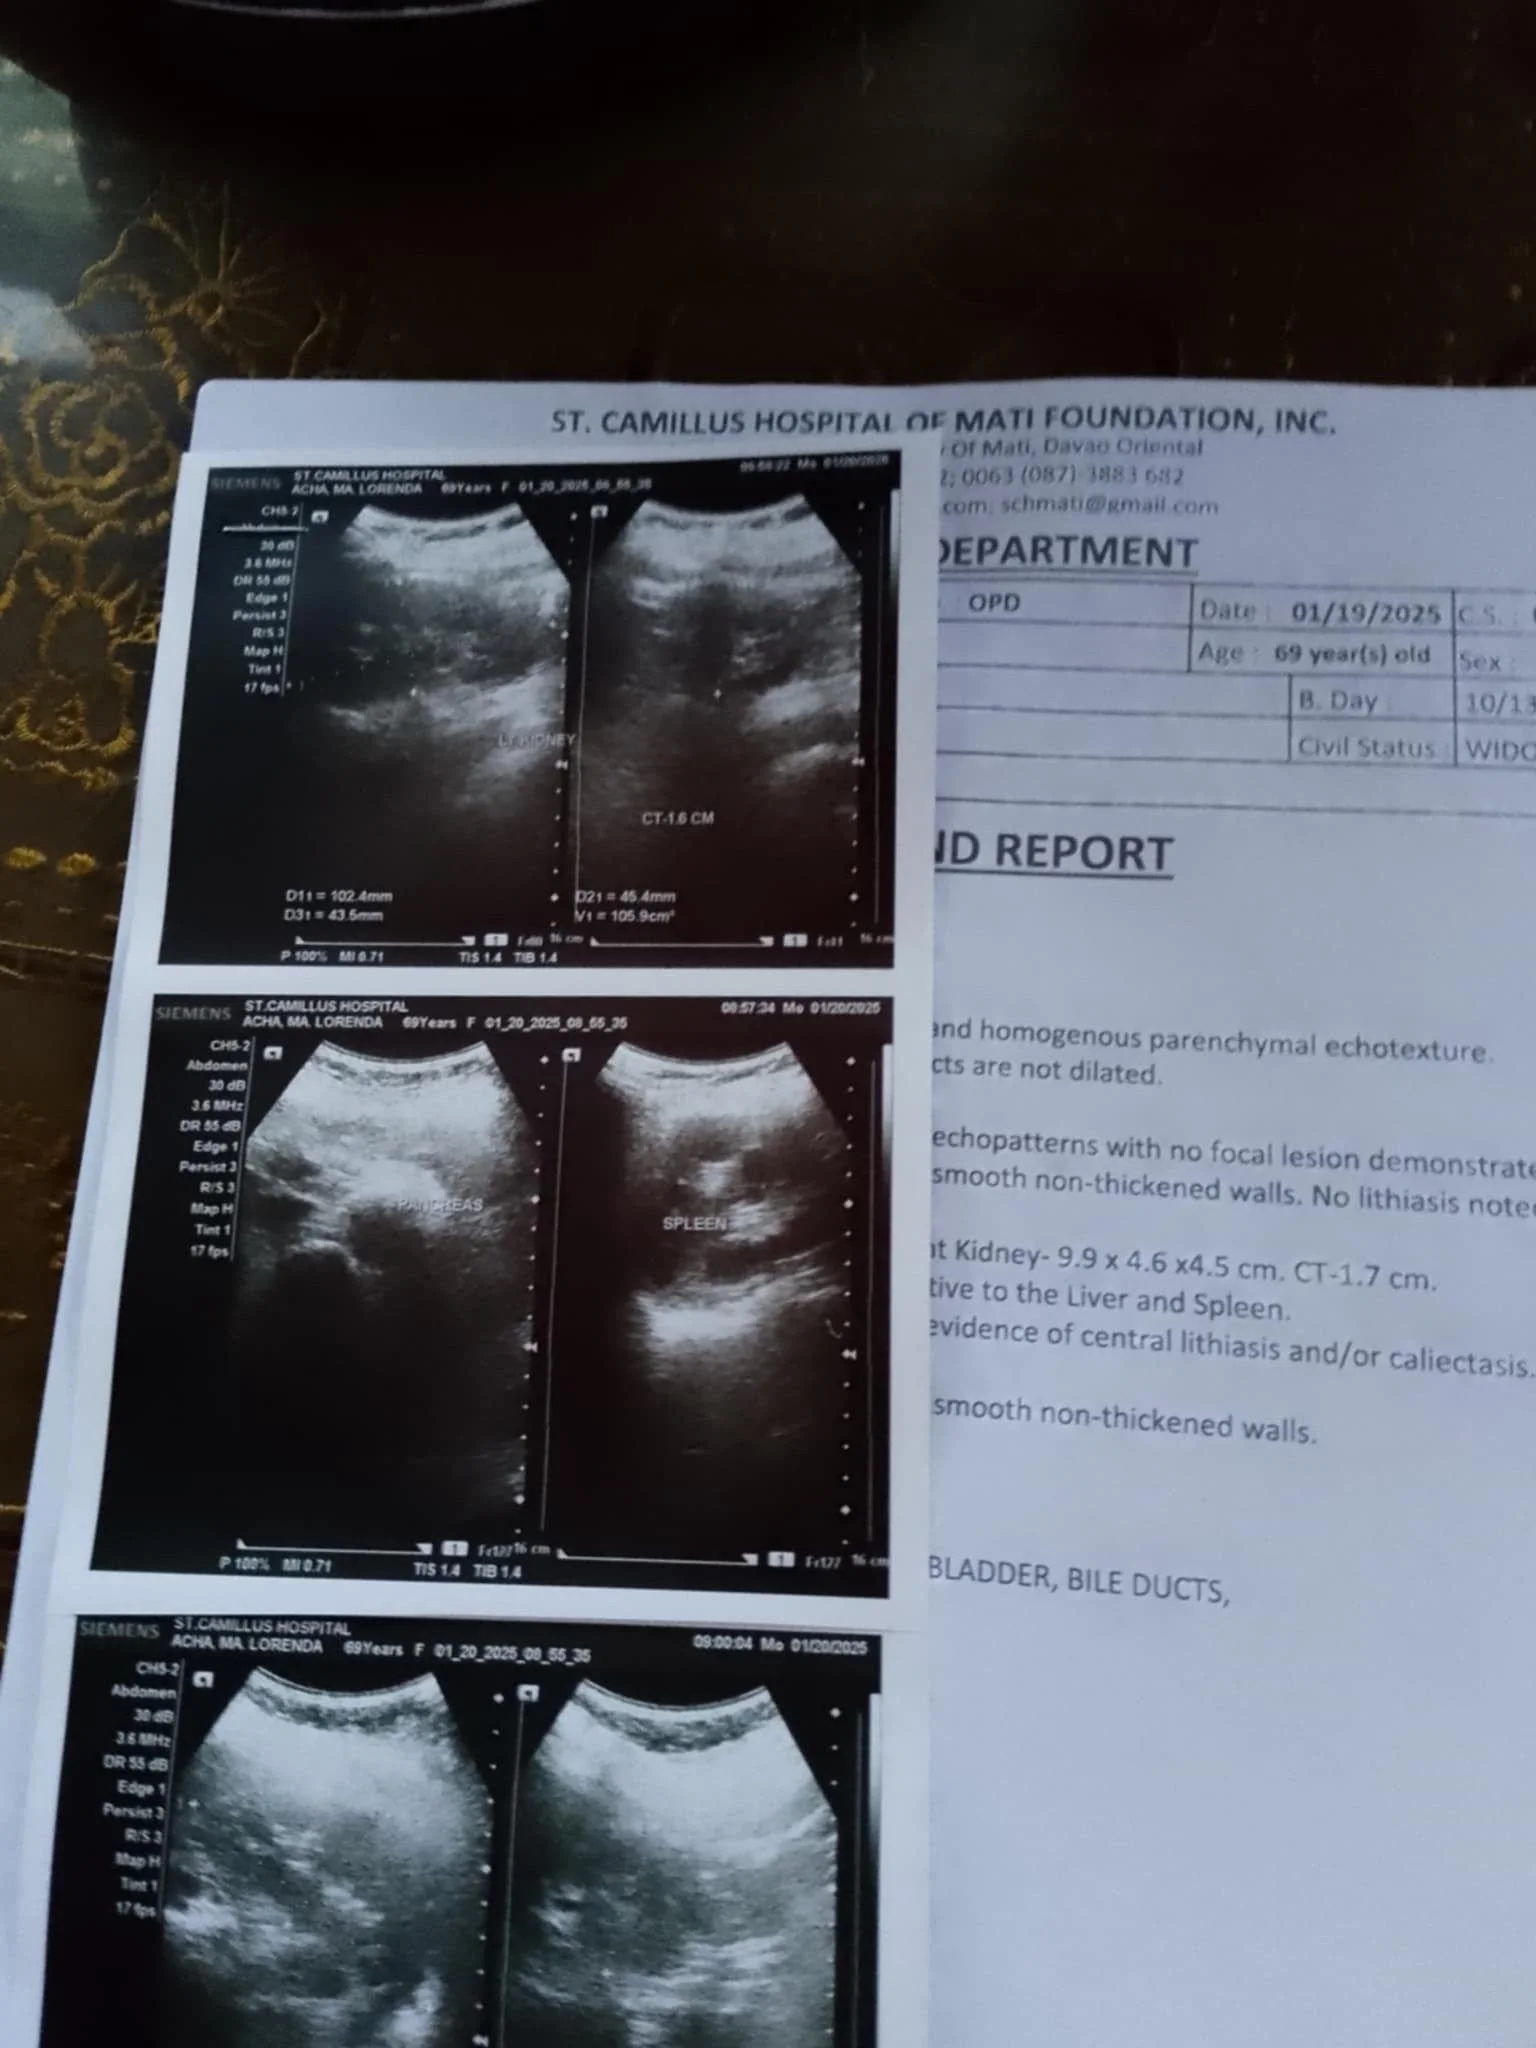

Jocelyn's Mom Receives Assistance for Ultrasound and Check-Up

Through the generous support of the foundation, Jocelyn's mom was able to receive much-needed cash assistance for her ultrasound and check-up. This assistance not only eased her financial burden but also ensured that she could access the essential medical care needed for her health and well-being. The foundation is proud to be a part of her journey towards better health and is committed to continuing to provide support to those in need.